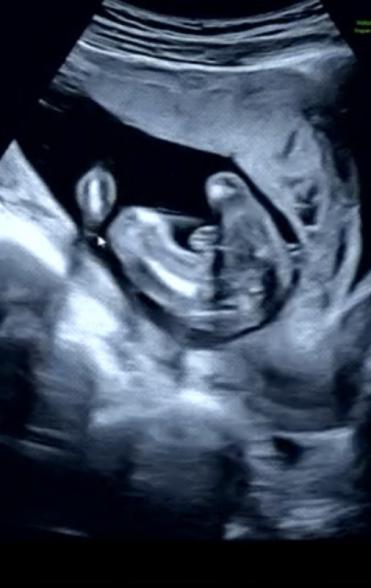

17w5d、性別は?

13wに胎児ドックを行った時には男の子かもと言われていましたが

17wでの検診の時には女の子だと言われました!

次の検診まで確定ではないとは言われていますが、、

赤ちゃんの性別についてですね。

拝見していて、はっきりと男の子のシンボルはわからず、女の子のサインとされるお股のあたりに見られるようになる葉っぱのマーク、サインが、添付をしてくださったものからは分かりませんでした。